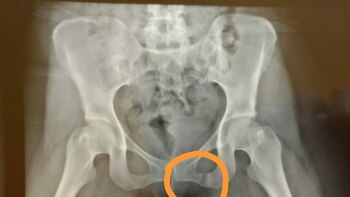

Lamberti sufrió una "fractura de rama izquierda de pelvis y fractura de dos vértebras de la columna" y deberá cuidarse por meses las heridas. "No me quise suicidar. Me quise salvar", resumió Verónica en su texto. "Hubo un día en mi vida en el que me juré que nunca más me iban a tocar un pelo sin mi consentimiento. Desde ese momento siempre pensé que si alguien entraba a robar a mi casa me iba a tirar por la ventana. Llegó el día, y lo que siempre dije sin pensar que podía ser real, sucedió".